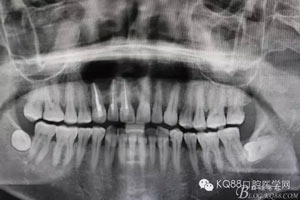

圖1.術(shù)前全景片檢查:11、12、13根尖區(qū)橢圓形陰影,邊界清楚,單囊影。初步診斷:頜骨囊腫

圖13.術(shù)后的全景片影像檢查: